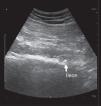

El síndrome piriforme es una causa poco frecuente de dolor de espalda y miembros inferiores. Algunas de las opciones de tratamiento incluyen la inyección del músculo piriforme con anestésicos locales y corticoides. Se han descrito varias técnicas de inyección. Las técnicas ecoguiadas permiten la visualización directa del músculo y la inyección en tiempo real. Se presenta una serie de 5 pacientes cuya clínica es compatible con síndrome piriforme, que no han mejorado tras tratamiento farmacológico. Se optó por la inyección del músculo piriforme con anestésicos locales y corticoides mediante un nuevo abordaje ecoguiado más sencillo técnicamente, basado en la técnica estándar. En los 5 pacientes se apreció una mejoría del dolor medido por la escala verbal numérica tras la inyección. Solo en un caso se presentó como complicación una ciatalgia que mejoró espontáneamente en 10 días. En los demás pacientes no se observaron complicaciones tras la inyección. Se describe una variante de la técnica ecoguiada recomendada en la inyección del músculo piriforme, más sencilla de realizar, con un buen perfil de seguridad y con buenos resultados clínicos.

Piriformis syndrome is an uncommon cause of buttock and leg pain. Some treatment options include the injection of piriformis muscle with local anesthetic and steroids. Various techniques for piriformis muscle injection have been described. Ultrasound allows direct visualization and real time injection of the piriformis muscle. We describe 5 consecutive patients, diagnosed of piriformis syndrome with no improvement after pharmacological treatment. Piriformis muscle injection with local anesthetics and steroids was performed using an ultrasound technique based on a standard technique. All 5 patients have improved their pain measured by numeric verbal scale. One patient had a sciatic after injection that improved in 10 days spontaneously. We describe an ultrasound-guided piriformis muscle injection that has the advantages of being effective, simple, and safe.